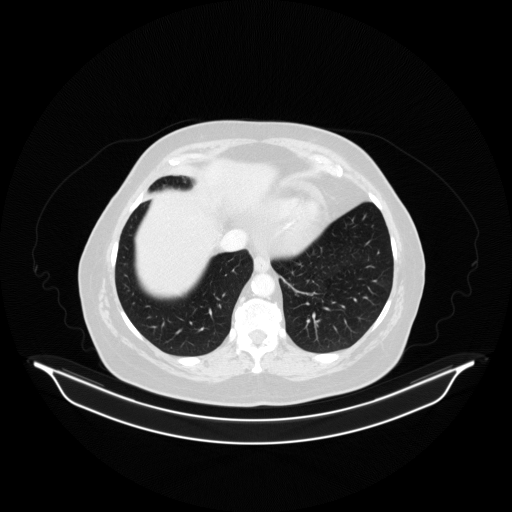

Original VENOUS CT scan

Full window (WL 1023.5, WW 4095 β†’ Low βˆ’1024, High +3071)

Lung window (WL -600, WW 1500 β†’ Low βˆ’1350, High +150)

Mediastinum window (WL 40, WW 400 β†’ Low βˆ’160, High +240)